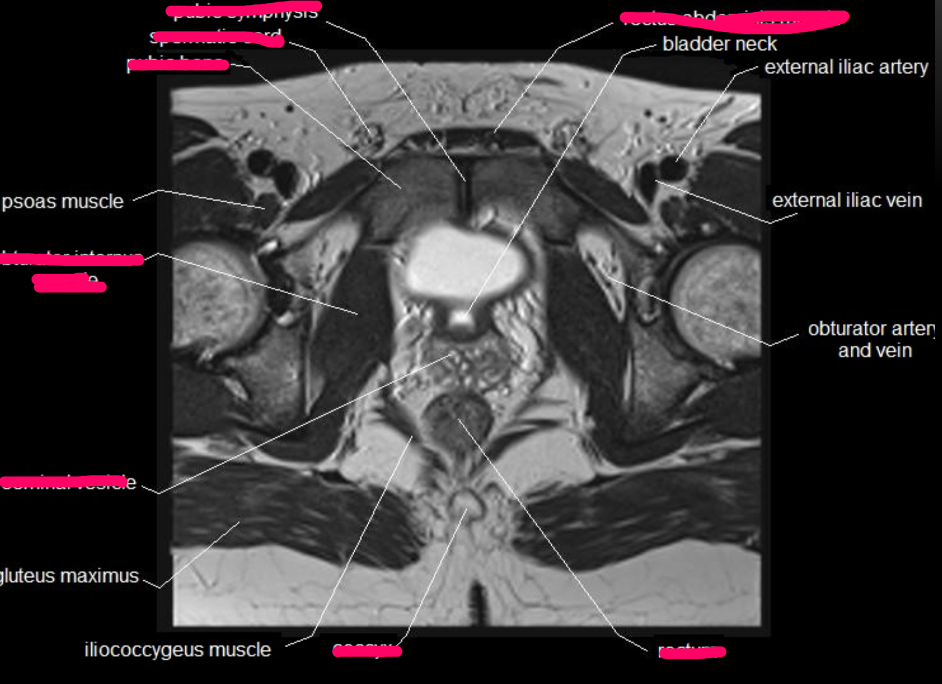

What type of imaging modality is this & fill in the blanks

MRI prostate, axial